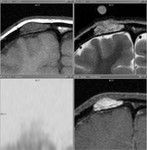

[画像診断]副甲状腺腺腫の存在診断、局在診断について(US, CT, MRI, RIの対比) 2011-02-28

[詳細は「タカ派の画像診断医」へ)